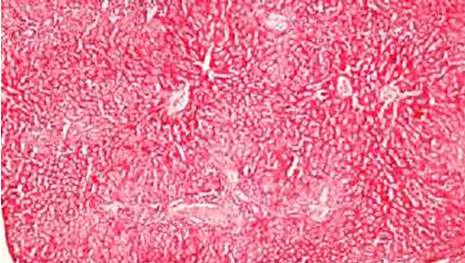

Внешний вид нормальных и деградированных тканей различных органов показан на рисунках. Наблюдались органы: печень, головной , легкие.

Деградация ткани Печени при увеличении х400